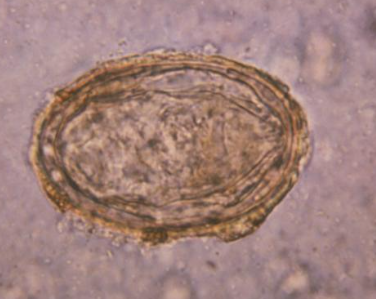

Taenia spp. - jajo

100x